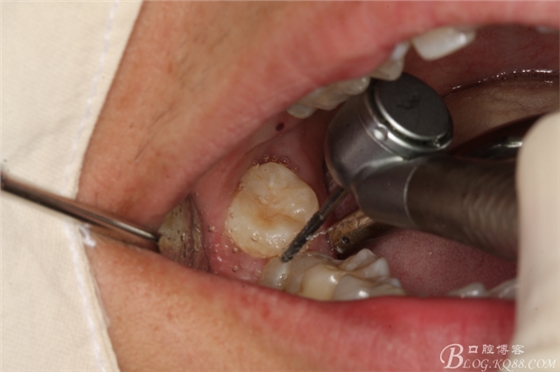

圖7.不切開(kāi)、不翻瓣、利用有限空間直接高速牙鉆分牙